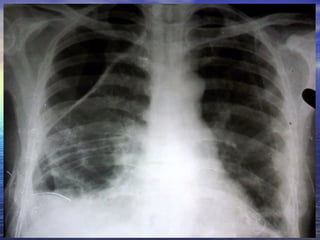

30 YEAR OLD MALE CAME TO OPD WITH COMPLAINTS OF BREATHLESSNESS 1 MONTH DURATION. NOW INCREASED FOR 2 DAYS H/O COUGH WITH EXPECTORATION 1 MONTH CHRONIC ALCOHOLIC AND SMOKER 15 YEARS

CHEST X RAY PA VIEW ADEQUATE INSPIRATION CENTRING, PATIENT POSITION -  NORMAL EXPOSURE/PENETRATION -  ADEQUQTE TRACHEA POSITION -  MIDLINE HEART AND MEDIASTINUM –  NORMAL PLEURAL SPACE  –  HYDROPNEUMOTHORAX  ON THE LEFT SIDE  EVIDENCED BY THE CONVEX  OUTSIDE BORDER OF  LUNG WITH VISCERAL PLEURA AND AIR FLUID LEVEL ? BULLAE/ ?LOCULATED HYDROPNEUMOTHORAX  SEEN  ON RIGHT SIDE EVIDENCED BY CONVEX INWARDS  MARGINS OF THEIR WALLS WITH AIR FLUID LEVEL COSTOPHRENIC ANGLES  BLUNTED BILATERALLY  CARDIOPHRENIC ANGLES  FREE HILA DENSITY, POSITION, SHAPE -  NORMAL SOFT TISSUES –  NORMAL BONES-  NORMAL Imp:LEFT HYDROPNEUMOTHORAX  RIGHT BULLOUS DISEASE/HYDROPNEUMOTHORAX WITH ?PLEURAL THICKENING

CHEST X RAYPA VIEW ADEQUATE INSPIRATION CENTRING, PATIENT POSITION - NORMAL EXPOSURE/PENETRATION - ADEQUQTE TRACHEA POSITION - MIDLINE HEART AND MEDIASTINUM – NORMAL PLEURAL SPACE – HYDROPNEUMOTHORAX ON THE LEFT SIDE EVIDENCED BY THE CONVEX OUTSIDE BORDER OF LUNG WITH VISCERAL PLEURA AND AIR FLUID LEVEL ? BULLAE/ ?LOCULATED HYDROPNEUMOTHORAX SEEN ON RIGHT SIDE EVIDENCED BY CONVEX INWARDS MARGINS OF THEIR WALLS WITH AIR FLUID LEVEL COSTOPHRENIC ANGLES BLUNTED BILATERALLY CARDIOPHRENIC ANGLES FREE HILA DENSITY, POSITION, SHAPE - NORMAL SOFT TISSUES – NORMAL BONES- NORMAL Imp:LEFT HYDROPNEUMOTHORAX RIGHT BULLOUS DISEASE/HYDROPNEUMOTHORAX WITH ?PLEURAL THICKENING